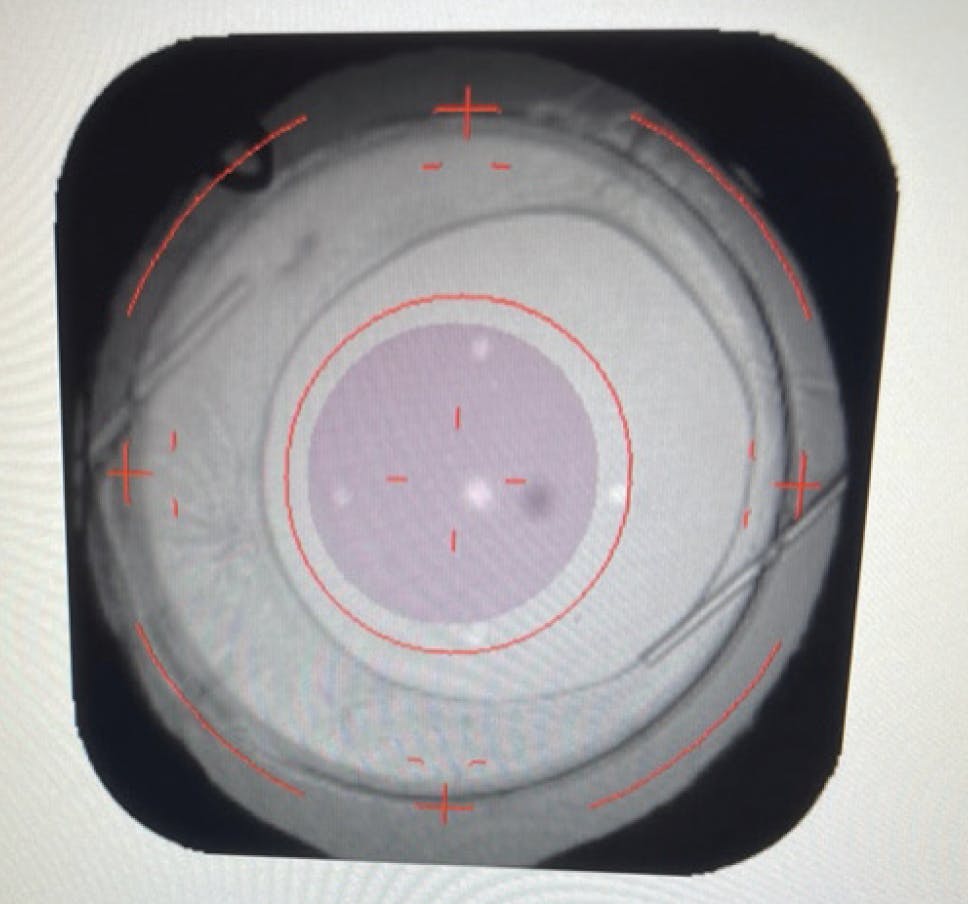

Light adjustment treatment was performed 3 weeks after the patient’s last surgery (Figure 4). The goal was to optimize distance vision in the right eye and target -1.00 D in the left eye. After the adjustments and lock-in treatment of the LAL, her UCVA was 20/20 OD and 20/20 and J2 OS.

Figure 4. Photograph of the Light Delivery Device (RxSight) interface showing the LAL and tip of the Ahmed tube before light adjustment treatment of the right eye.